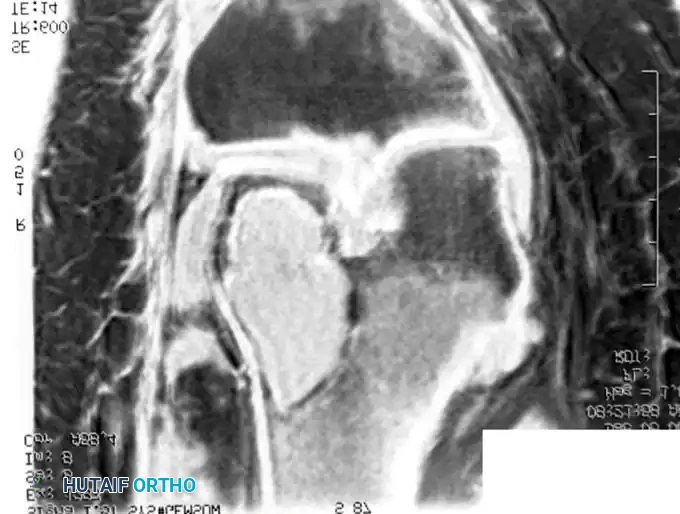

BENIGN TUMORS AND TUMOR-LIKE LESIONS Surgical Diagram

Radiograph and MRI of a shoulder with synovial chondromatosis, demonstrating multiple intra-articular ossified loose bodies. The gross specimen photograph highlights the sheer volume of cartilaginous bodies resected during synovectomy.

Surgical Management: Treatment dictates the removal of all loose bodies combined with an extensive anterior and posterior synovectomy. While arthroscopic management is preferred for the knee and shoulder, open arthrotomy is often required for the hip to ensure complete clearance and prevent secondary osteoarthritis.